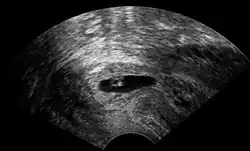

| Vaginal ultrasonography of a cervical pregnancy at a gestational age of five weeks. See image below for details of the visible structures.[1] | |

The diagnosis is made in asymptomatic pregnant women either by inspection seeing a bluish discolored cervix or, more commonly, by obstetric ultrasonography. A typical non-specific symptom is vaginal bleeding during pregnancy. Ultrasound will show the location of the gestational sac in the cervix, while the uterine cavity is "empty". Cervical pregnancy can be confused with a miscarriage when pregnancy tissue is passing through the cervix.